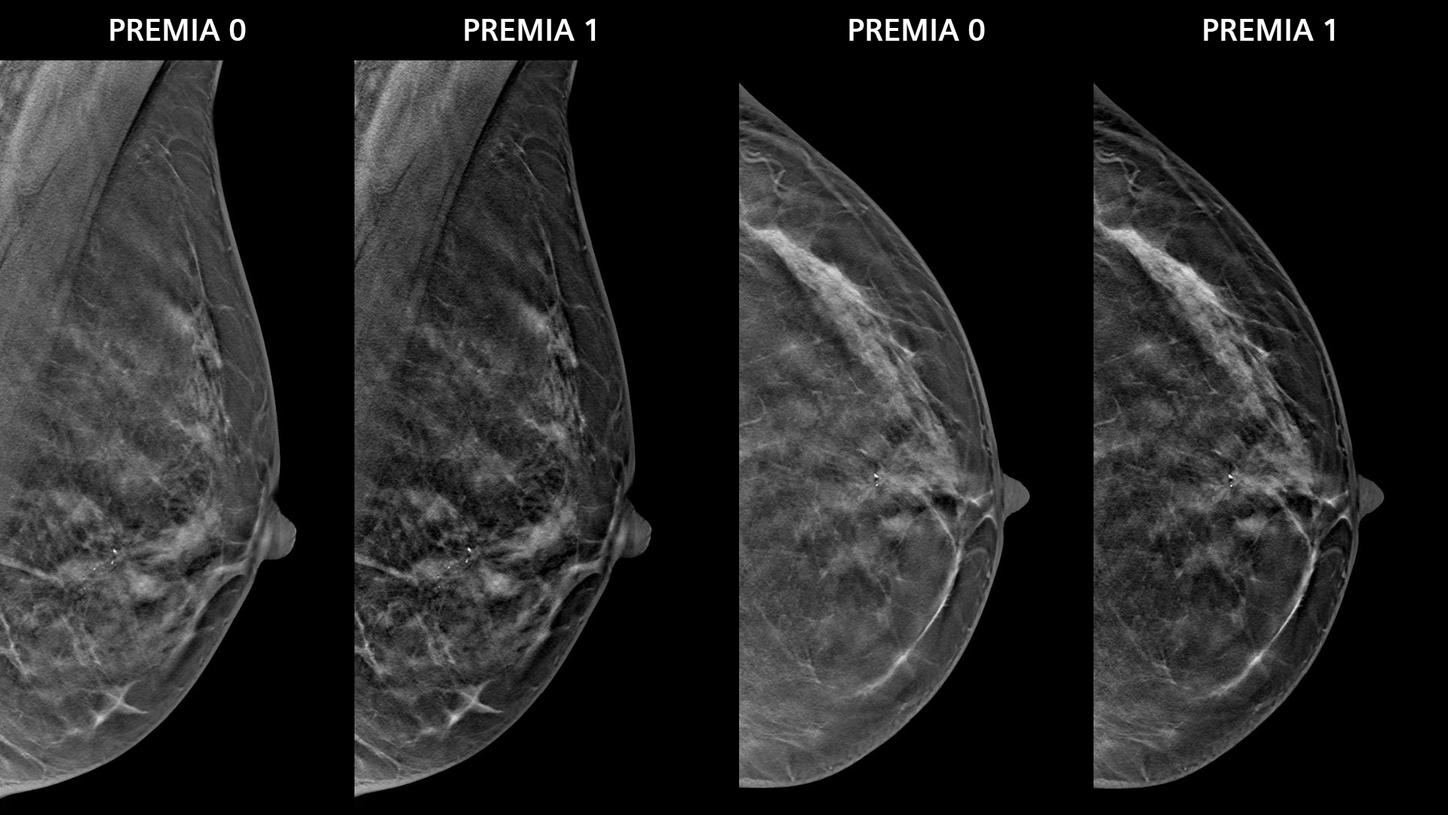

- PREMIA image reconstruction:

Improved image reconstruction framework- Reduce artifacts and enhance visibility of calcifications and lesions

- Comfortable transition from 2D and narrow-angle systems, thanks to customizable image impressions

Image impression

5 different options for contrast and image sharpness for FFDM and synthesized 2D.

2 options for contrast and image sharpness for tomosynthesis projections.Angular range and sweep